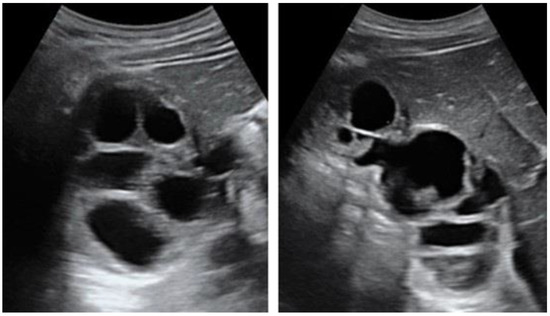

Polycystic Liver